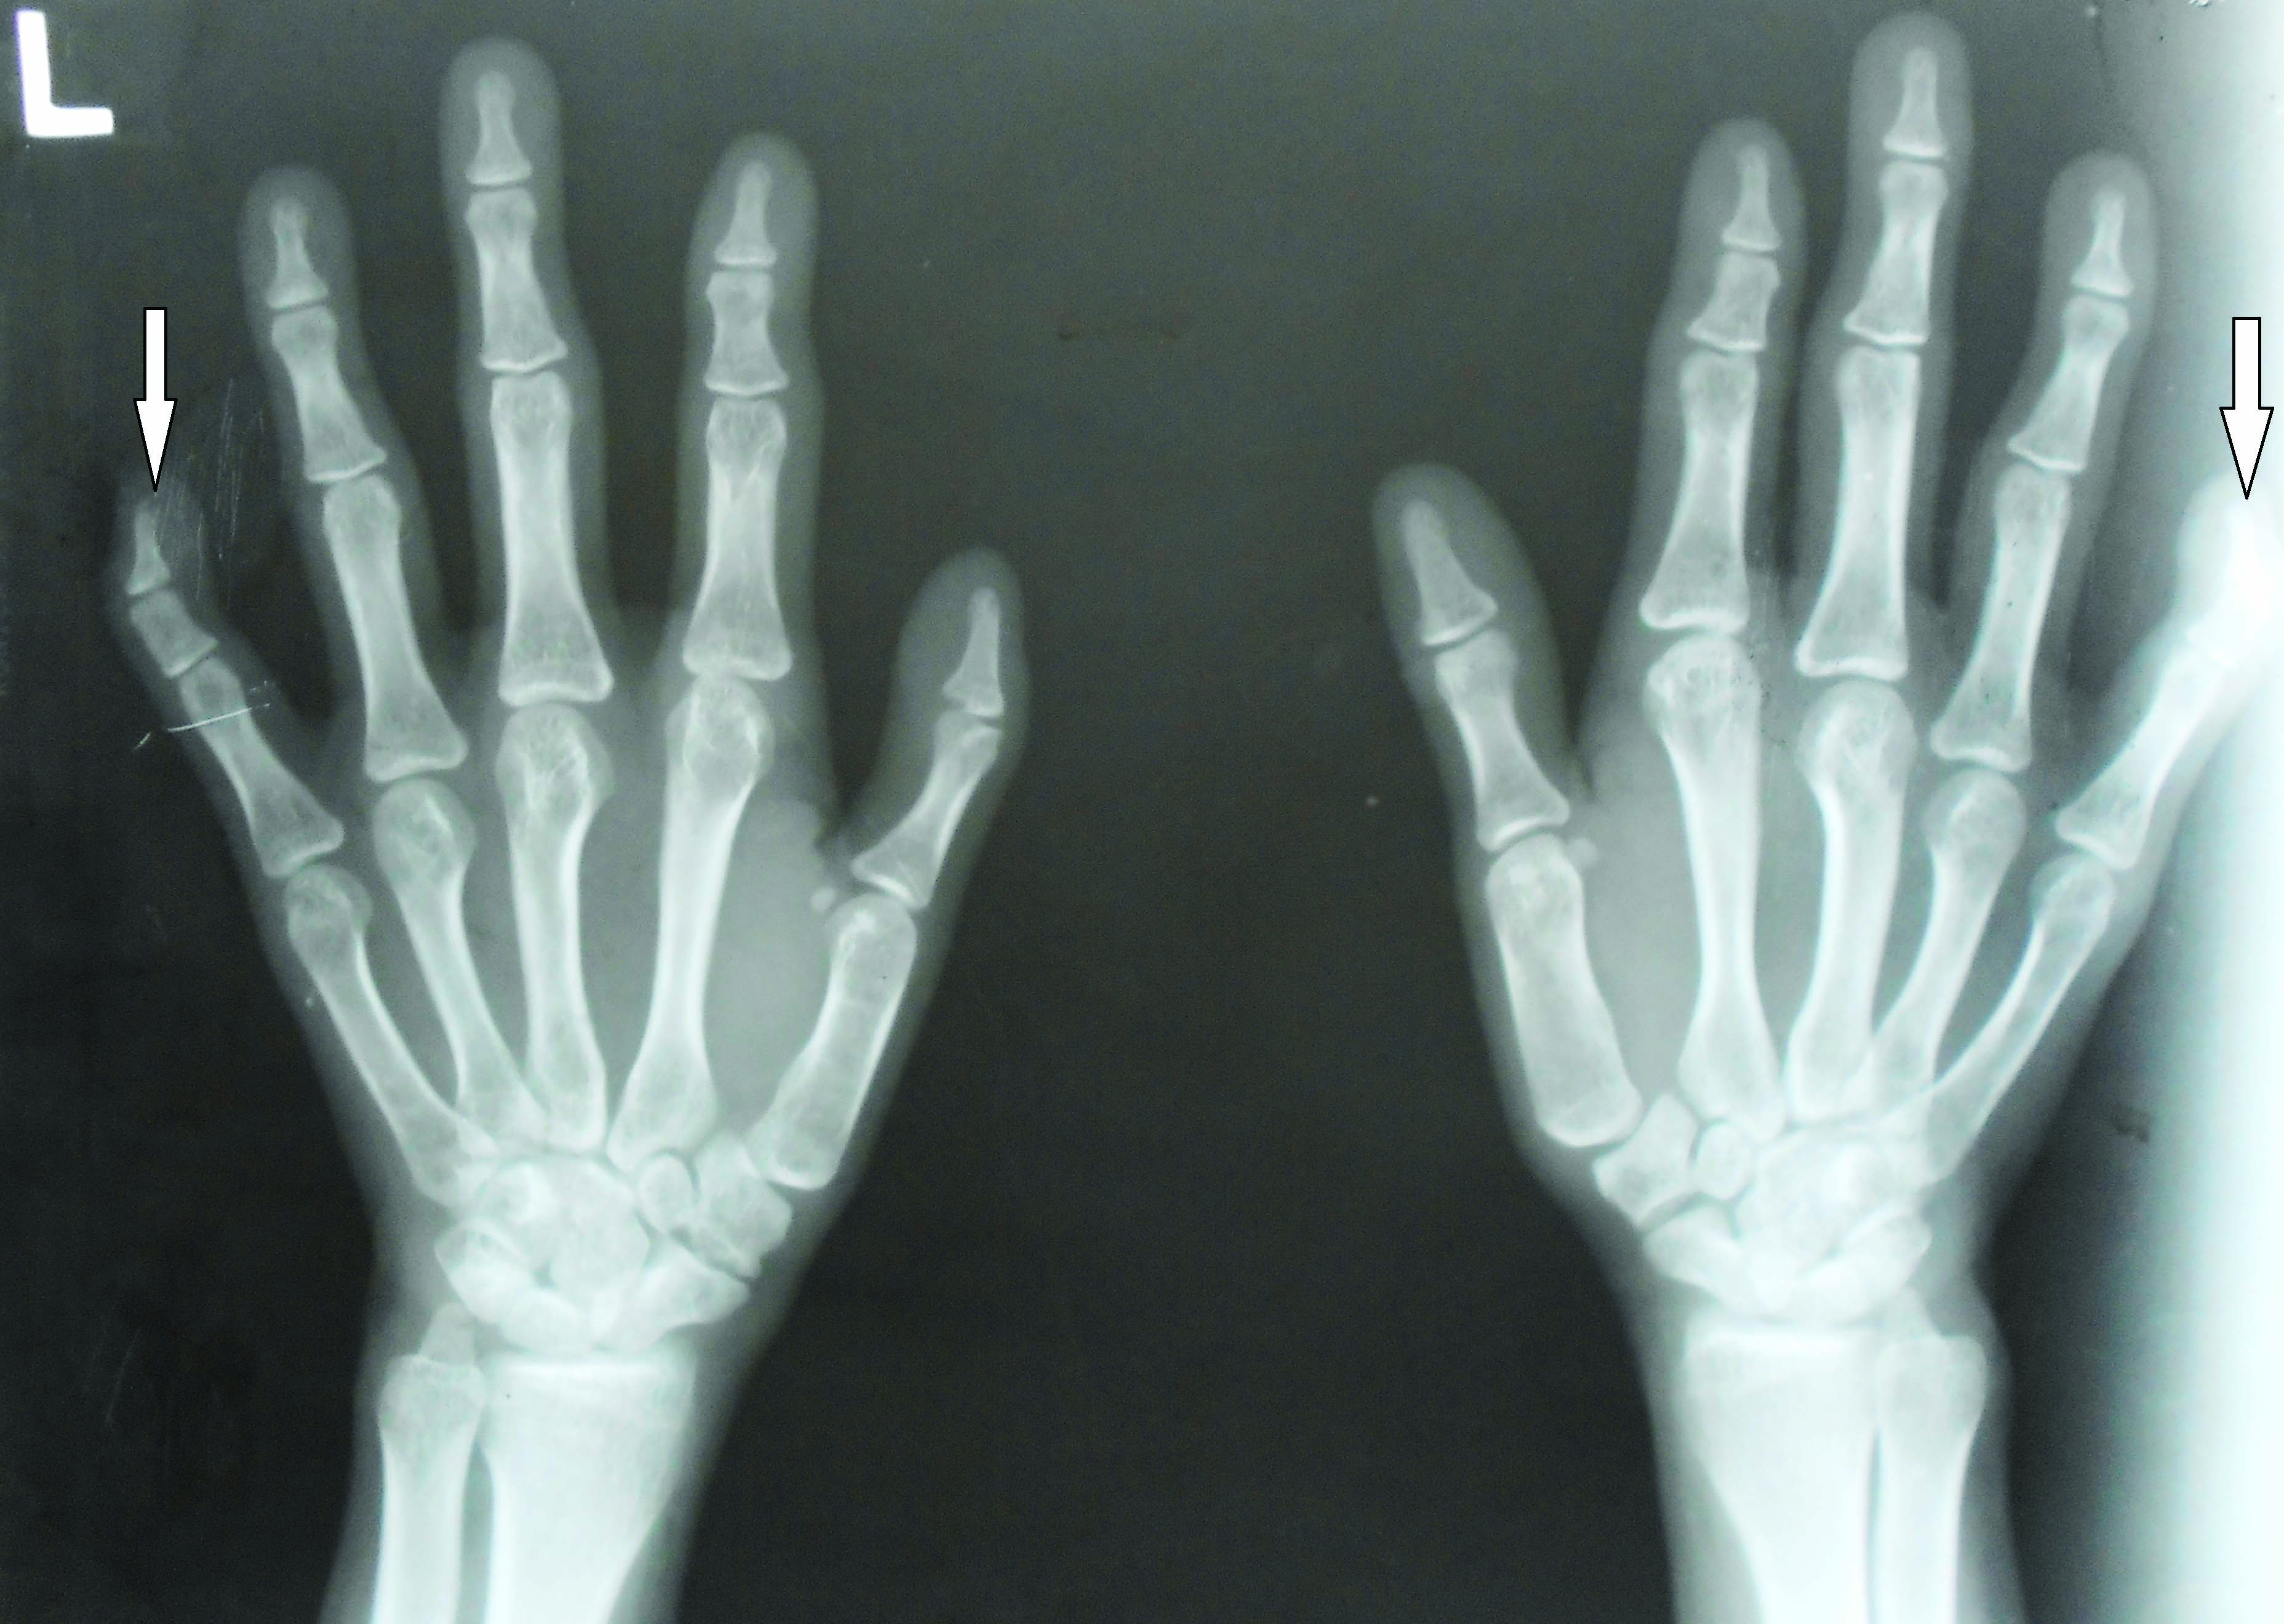

Clinodactyly of fifth finger of right and left hand shown by black Hand Wrist Radiograph In Orthodontics Several guidelines provided by the ada and the american academy of oral and maxillofacial radiology on the use of cbct and other. The hand wrist radiograph is considered to be the most standardized method of skeletal assessment. The hand and wrist radiograph help in estimating the skeletal age of bone for determining the physical maturation status of the child. The. Hand Wrist Radiograph In Orthodontics.

From www.jcdr.net